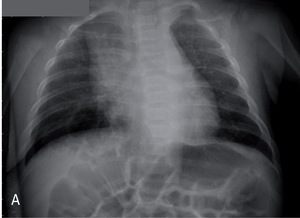

Rycina 3. Zdjęcia przeglądowe tylno-przednie (A) i boczne (B) trzymiesięcznego chłopca z sekwestracją wewnątrzpłatową dolnego płata prawego.